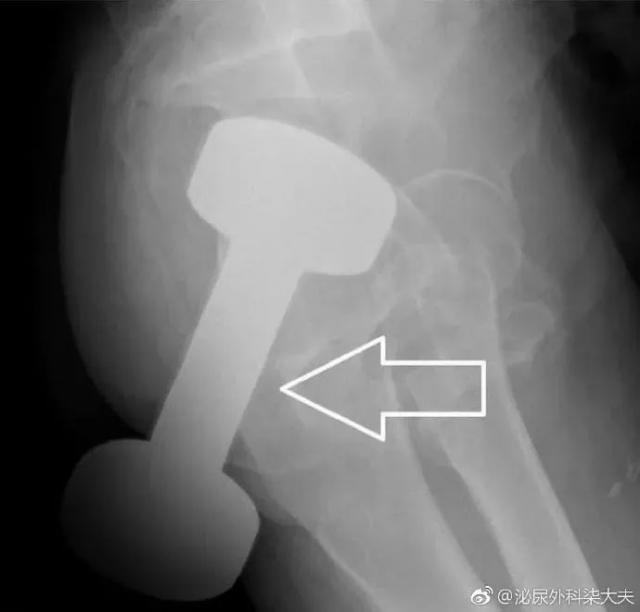

一位 50 多岁的男子发现了这种新奇玩法,把重达 10 斤的哑铃塞进了肛门。

罗非鱼直肠,罗非鱼塞进直肠多长时间